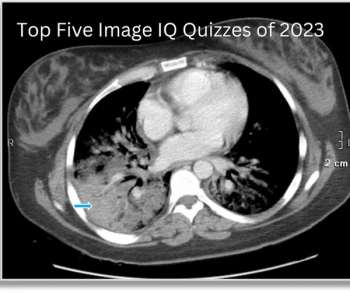

Catch up on the most well-read Image IQ quizzes from 2023.